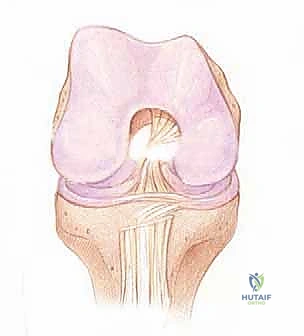

التشريح الدقيق للرباط الصليبي الأمامي والميكانيكا الحيوية

لفهم أهمية جراحة إعادة البناء، يجب أولاً الغوص في التشريح المعقد للرباط الصليبي الأمامي. هو ليس مجرد شريط مطاطي، بل نسيج حيوي ديناميكي يلعب دور القائد في توجيه حركة الركبة.

الموقع والتركيب النسيجي

يقع الرباط الصليبي الأمامي في قلب مفصل الركبة، ويمتد بشكل مائل من الشق بين اللقمتين (Intercondylar notch) في عظم الفخذ، نزولاً إلى السطح العلوي لعظم الظنبوب (القصبة).

الحزم التشريحية (Anatomical Bundles)

من الناحية الوظيفية والتشريحية، لا يعمل الرباط كوحدة واحدة، بل ينقسم إلى حزمتين رئيسيتين تعملان بتناغم عجيب:

1. الحزمة الأمامية الإنسية (Anteromedial Bundle - AM): هذه الحزمة تكون مشدودة بشكل رئيسي عندما تكون الركبة في وضعية الانثناء (Flexion). وظيفتها الأساسية هي منع عظم القصبة من الانزلاق للأمام بعيداً عن عظم الفخذ.

2. الحزمة الخلفية الوحشية (Posterolateral Bundle - PL): تكون هذه الحزمة مشدودة عندما تكون الركبة في وضعية الاستقامة الكاملة (Extension). هذه الحزمة هي المسؤولة الأولى عن توفير الثبات الدوراني للركبة، وهي التي تمنع الركبة من الالتواء أثناء تغيير الاتجاه المفاجئ.